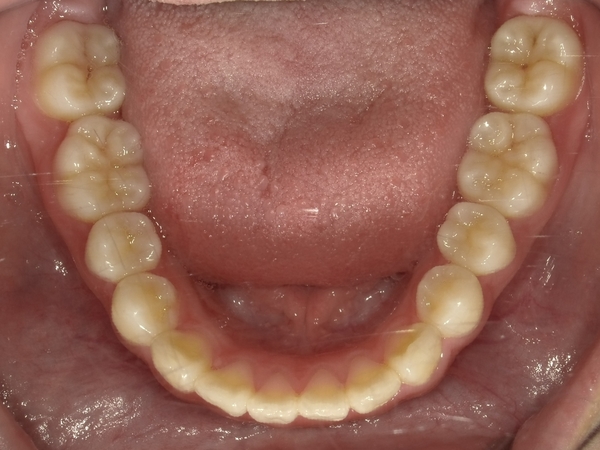

〇ご相談内容:歯のねじれが少し気になる〇矯正の種類:マウスピース型矯正「インビザライン」〇治療期間:14週間〇治療費用:44万円(税込)